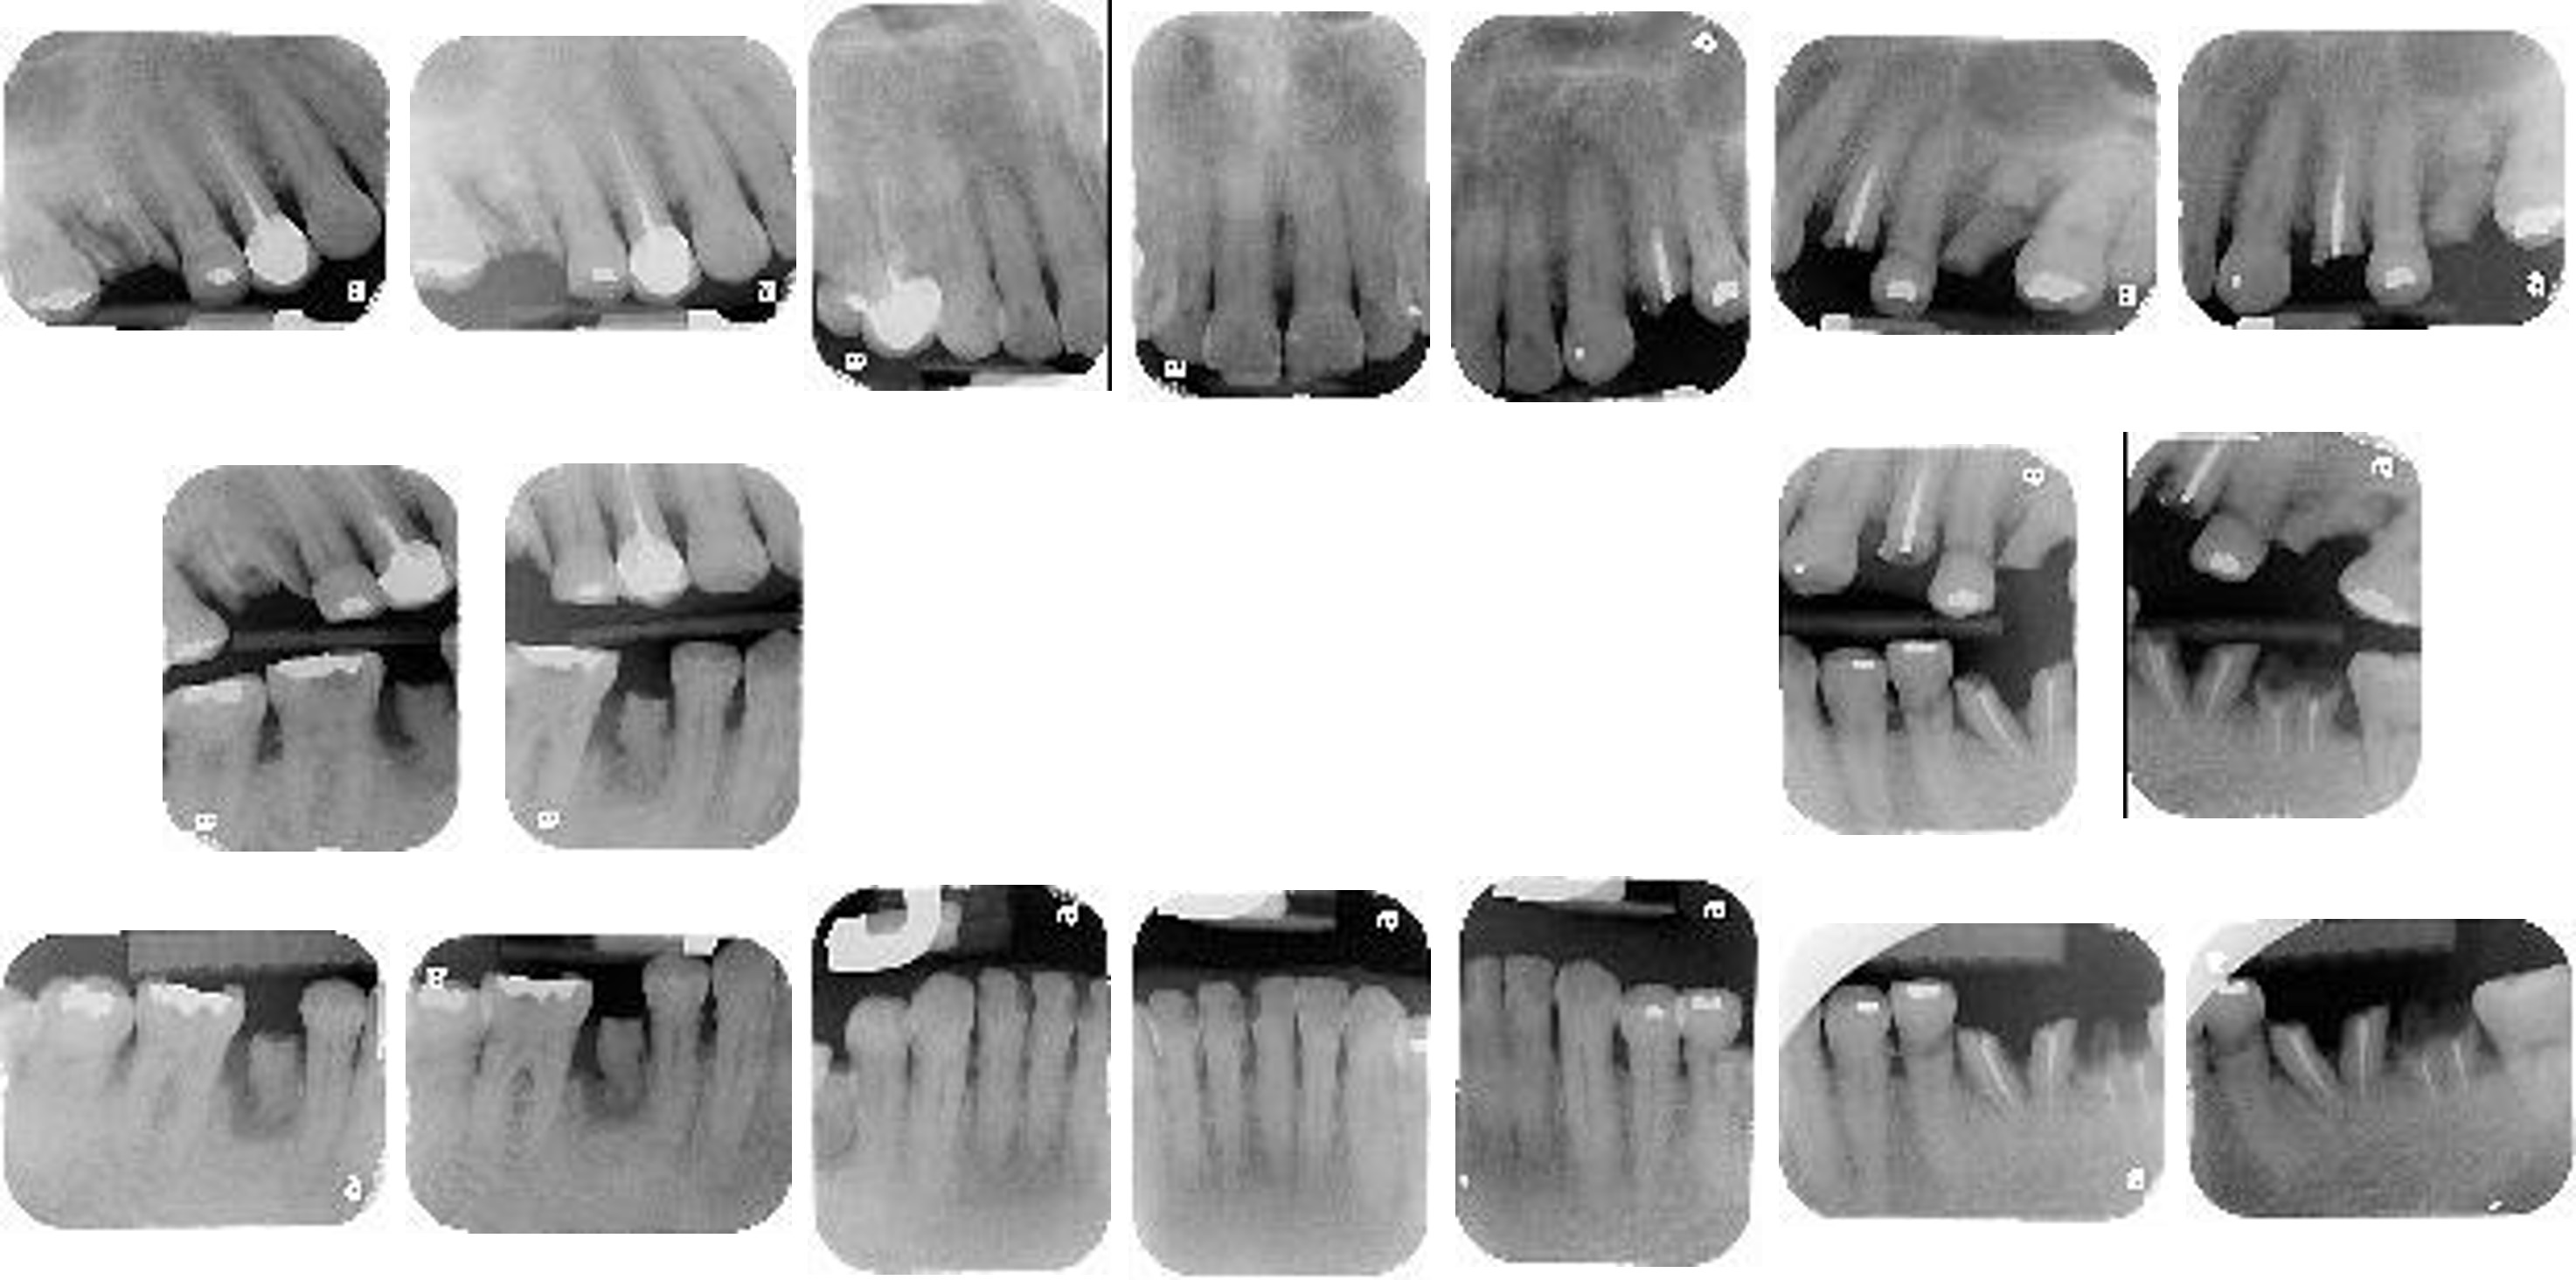

牙周檢查-X光

X光片拍攝:

拍攝全口根尖片X光片,了解牙周骨骼結構的破壞程度。